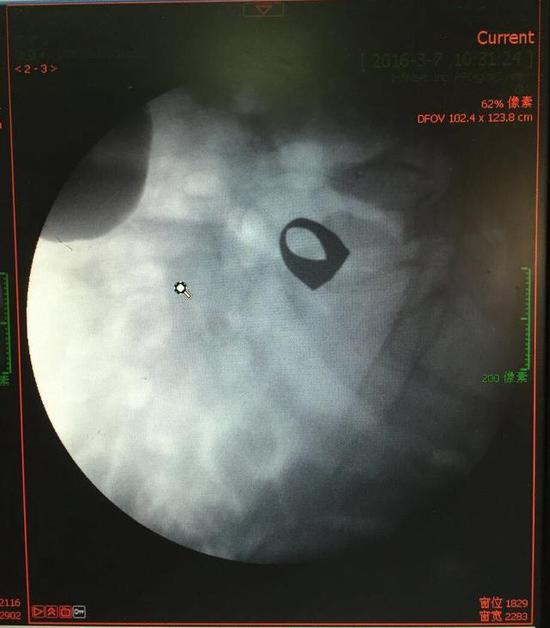

考慮到患者年齡較大,有冠心病,曾經(jīng)中過風(fēng),高血壓極高危級(jí),遂把老人安排在帶有監(jiān)護(hù)的病房,立即給予吸氧,補(bǔ)液等治療。醫(yī)院立刻開啟綠色通道,醫(yī)護(hù)人員專門陪伴病人做了增強(qiáng)CT,腹部平片,和碘水造影,確定戒指的位置。檢查結(jié)果提示戒指位于右下腹小腸內(nèi),距回盲瓣體表投影約5cm。

此時(shí)一個(gè)又一個(gè)大大的疑問出現(xiàn)在每個(gè)在場的醫(yī)護(hù)人員腦海中,戒指還在小腸里嗎?戒指在哪個(gè)位置呢?夏教授立刻聯(lián)系放射科,拍片子,發(fā)現(xiàn)戒指已經(jīng)移動(dòng)了,從右側(cè)移動(dòng)到了左側(cè)去了。放射科醫(yī)師建議,戒指有可能會(huì)繼續(xù)沿腸道下行,如果過了回盲瓣,就可以自行排出,免除手術(shù)痛苦。教授們采納了這個(gè)意見,立即給予促進(jìn)胃腸道動(dòng)力藥,枸櫞酸莫沙必利片,每日口服三次,另外配合灌腸治療,促進(jìn)腸道蠕動(dòng),利于戒指排出。